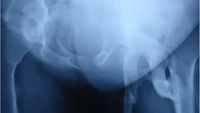

Benjolan-benjolan yang terasa nyeri muncul di punggung akibat massa keras dan kekakuan pada bahu, leher, serta pinggul kiri. Kondisi ini membuatnya juga sulit berjalan atau jongkok secara normal. (Foto: Journal of Medical Case Reports)

Pasien tidak sembuh total, tapi menjalani perawatan konservatif untuk membantu mengurangi perburukan gejala. Pasien sempat menjalani operasi pengangkatan tulang yang tumbuh secara tak normal di pinggul kiri, tapi justru terjadi pertumbuhan tulang yang lebih parah. (Foto: Journal of Medical Case Reports)